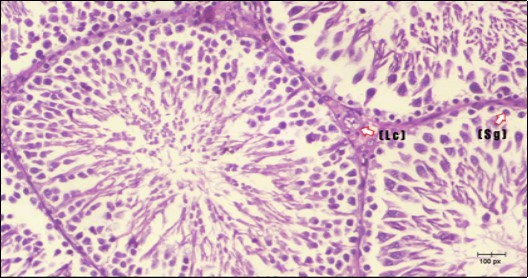

Testis Histopathological Observations

Histological examination of control rats' testis showed normal histological structure of the seminiferous tubules with an increase in the spermatogonia and other spermatocytes compared with the diabetic rats which showed an obvious decrease in the count of germinal cells generally and sloughing of germ cell in the lumen of seminiferous tubules in addition to absence of the mature sperms (Figure 3 and Figure 4). Rats tested of Fenugreek group and those treated with Glimepiride (Figure 5 and Figure 6) presented an increase in the number of spermatogenic cells and mature sperms with few focal necrotic cells. Whereas the combination therapy group showed normal histological structure of the seminiferous tubules with normal spermatogonia, presence of ledying cells and more mature of sperms (Figure 7). STZ reduced testosterone production, suggesting a decrease in the function of both Leydig (testosterone producing cell) and Sertoli (spermatogenesis) cells, which might be caused by a reduction in insulin secretion. These changes are probably due to increased Reactive Oxygen Species (ROS) production by accelerated Advanced Glycation End Products (AGE) formation 31 hexosamine and Protein Kinase C pathway. The administration of Fenugreek seeds to diabetic rats significantly decrease of sperm shape abnormality and improve the sperm count 32. Glimepiride reduced sperm abnormality and increased testis weights and sperm count by its antioxidant action 30. The potential protective efficacy of Fenugreek seed extract when added to Glimepiride was observed on reproductive systems.

Figure 3.Photomicrogragh of testis section of a control rat showing testicular tissue with seminiferous tubules separated by interstitial tissue with Ledying cells (arrow). Seminiferous tubules with complete spermatogenesis, Sertoli cell (dashed-arrow) and spermatozoa . (H&E) (40X).